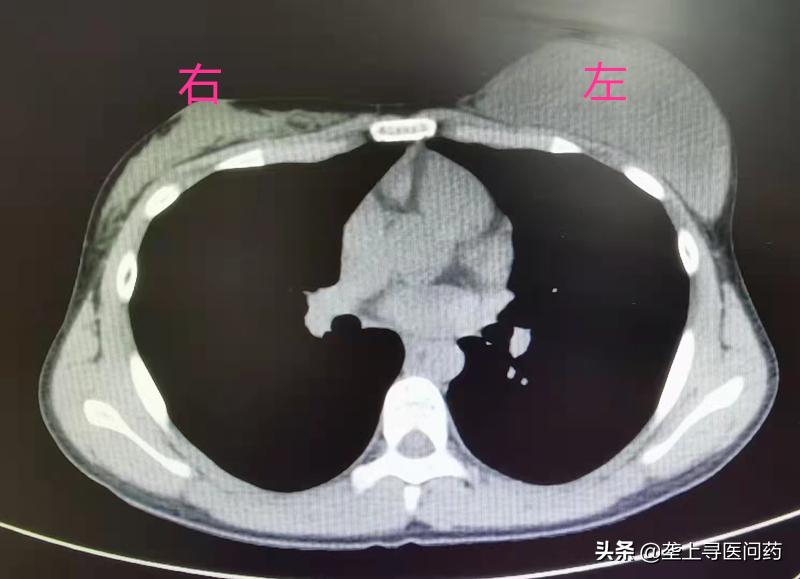

患者小雪(化名)家住汉川,一年半前,她自觉左侧胸部逐渐增大,正处于青春期的她以为是正常的生长发育就一直没有放到心上。春节期间,小雪外出打工的父母回汉川过年,妈妈聂女士在洗澡时发现女儿左右胸部大小差别巨大,感觉不对劲的聂女士赶紧带着小雪去了医院,在当地医院经乳腺彩超提示,左侧乳腺实质病灶有两个,大的约有9.2×3.0×8.6㎝,小的约有0.7×0.3㎝,怀疑恶性肿瘤可能。

为了进一步确诊和治疗,聂女士带着小雪来到了湖北省第三人民医院(湖北省中山医院)甲乳外科。接诊医生发现,小雪左侧胸部如成人大小,犹如乳房假体在内,右侧胸部还尚未发育,进一步完善相关检查后,建议小雪手术治疗。